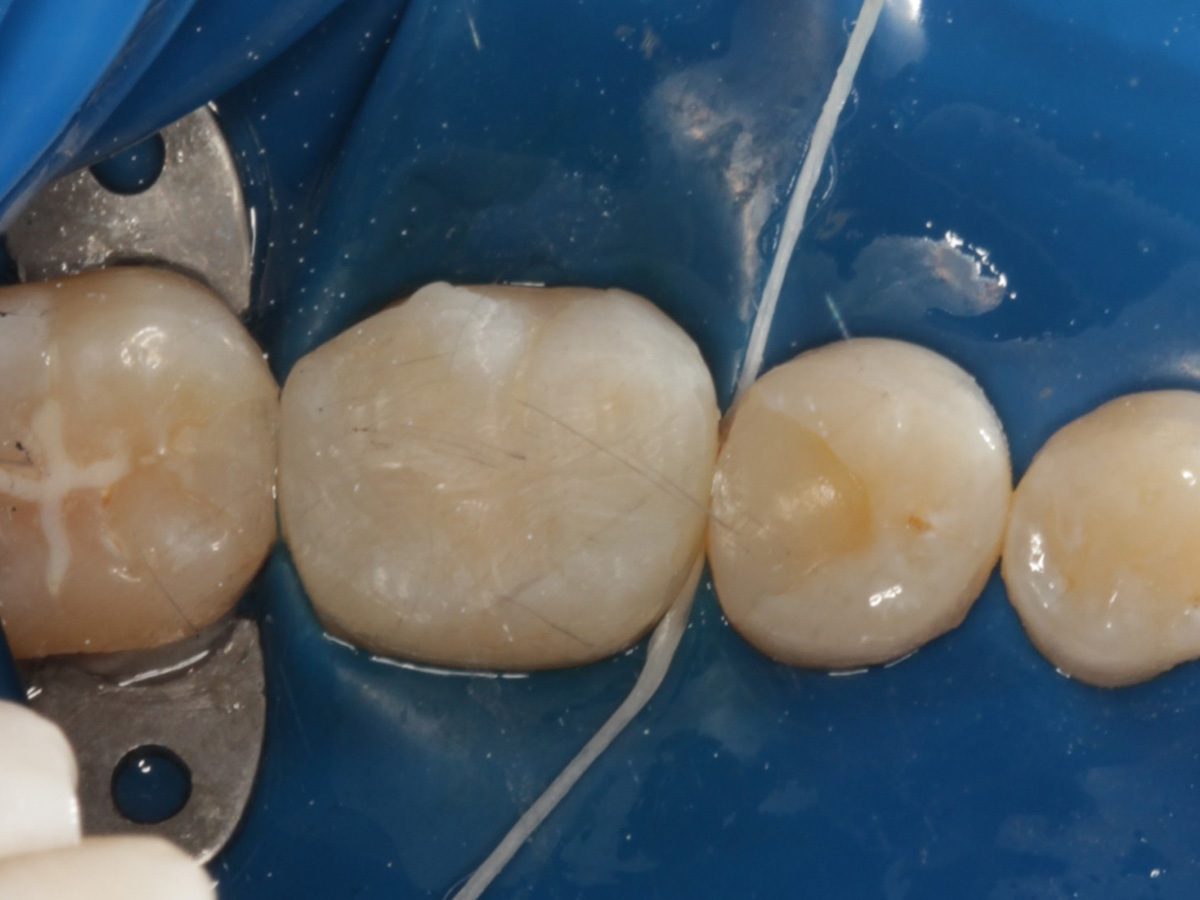

Kavitäten gefüllt (Injektion Moulding: Flowkomposit, erwärmtes Seitenzahnkomposit aus Karpule)

Abbildung 20

Abbildung 21

Zahnseidenkontrolle: kein Überschuss, satte Kontaktpunkte